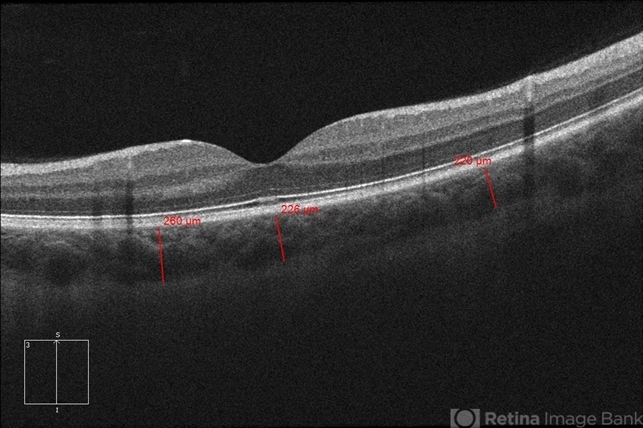

- 20-year-old white, male presented for initial evaluation with one week history of acute, sudden, painless loss of central vision in his right eye a week prior to presentation. - H/O short course of exogenous testosterone, Tamoxifen and Clomiphene intake ~ 2-3 weeks cycle, which was already stopped, prior to development of pt's symptoms. - H/O acute illness with generalized fatigue, malaise, URTI like symptoms and rash over the hands and chest, just prior to symptoms development, and upon further discussion, pt mentioned that few of his friends got sick around the same time. - Patient was seen the week prior by general ophthalmologist and was found to have SRF on OCT , diagnosed with CSCR and referred for retina evaluation. - ROS/ PMHx: Negative, healthy aside from the short illness described above - Denied any prior vision problems, similar episodes, trauma etc - VA Dsc OD: 20/400 OS:20/20 - anterior segment exam - unremarkable - posterior segment - macular RPE changes/ clumping with GA with no CME/ SRF or crystals OD, and unremarkable OS. - Pseudocolor and FAF photos: RPE changes/ clumps w/ GA and stippled autofluorescense OD, unremarkable OS. - HD SD-OCT: thickened choroid, thickened/ hypertrophied subfoveal RPE with hyper-reflective material on the apical side of the retinal pigment epithelium/apical debris, Subfoveal ellipsoid zone atrophy w/ intact ELM W/No CME or SRF OD, Unremarkable OS. - FA: Dye not available - ICG: deferred - mf-ERG & VF - patient rescheduled